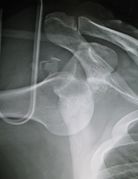

- Plain film X-ray